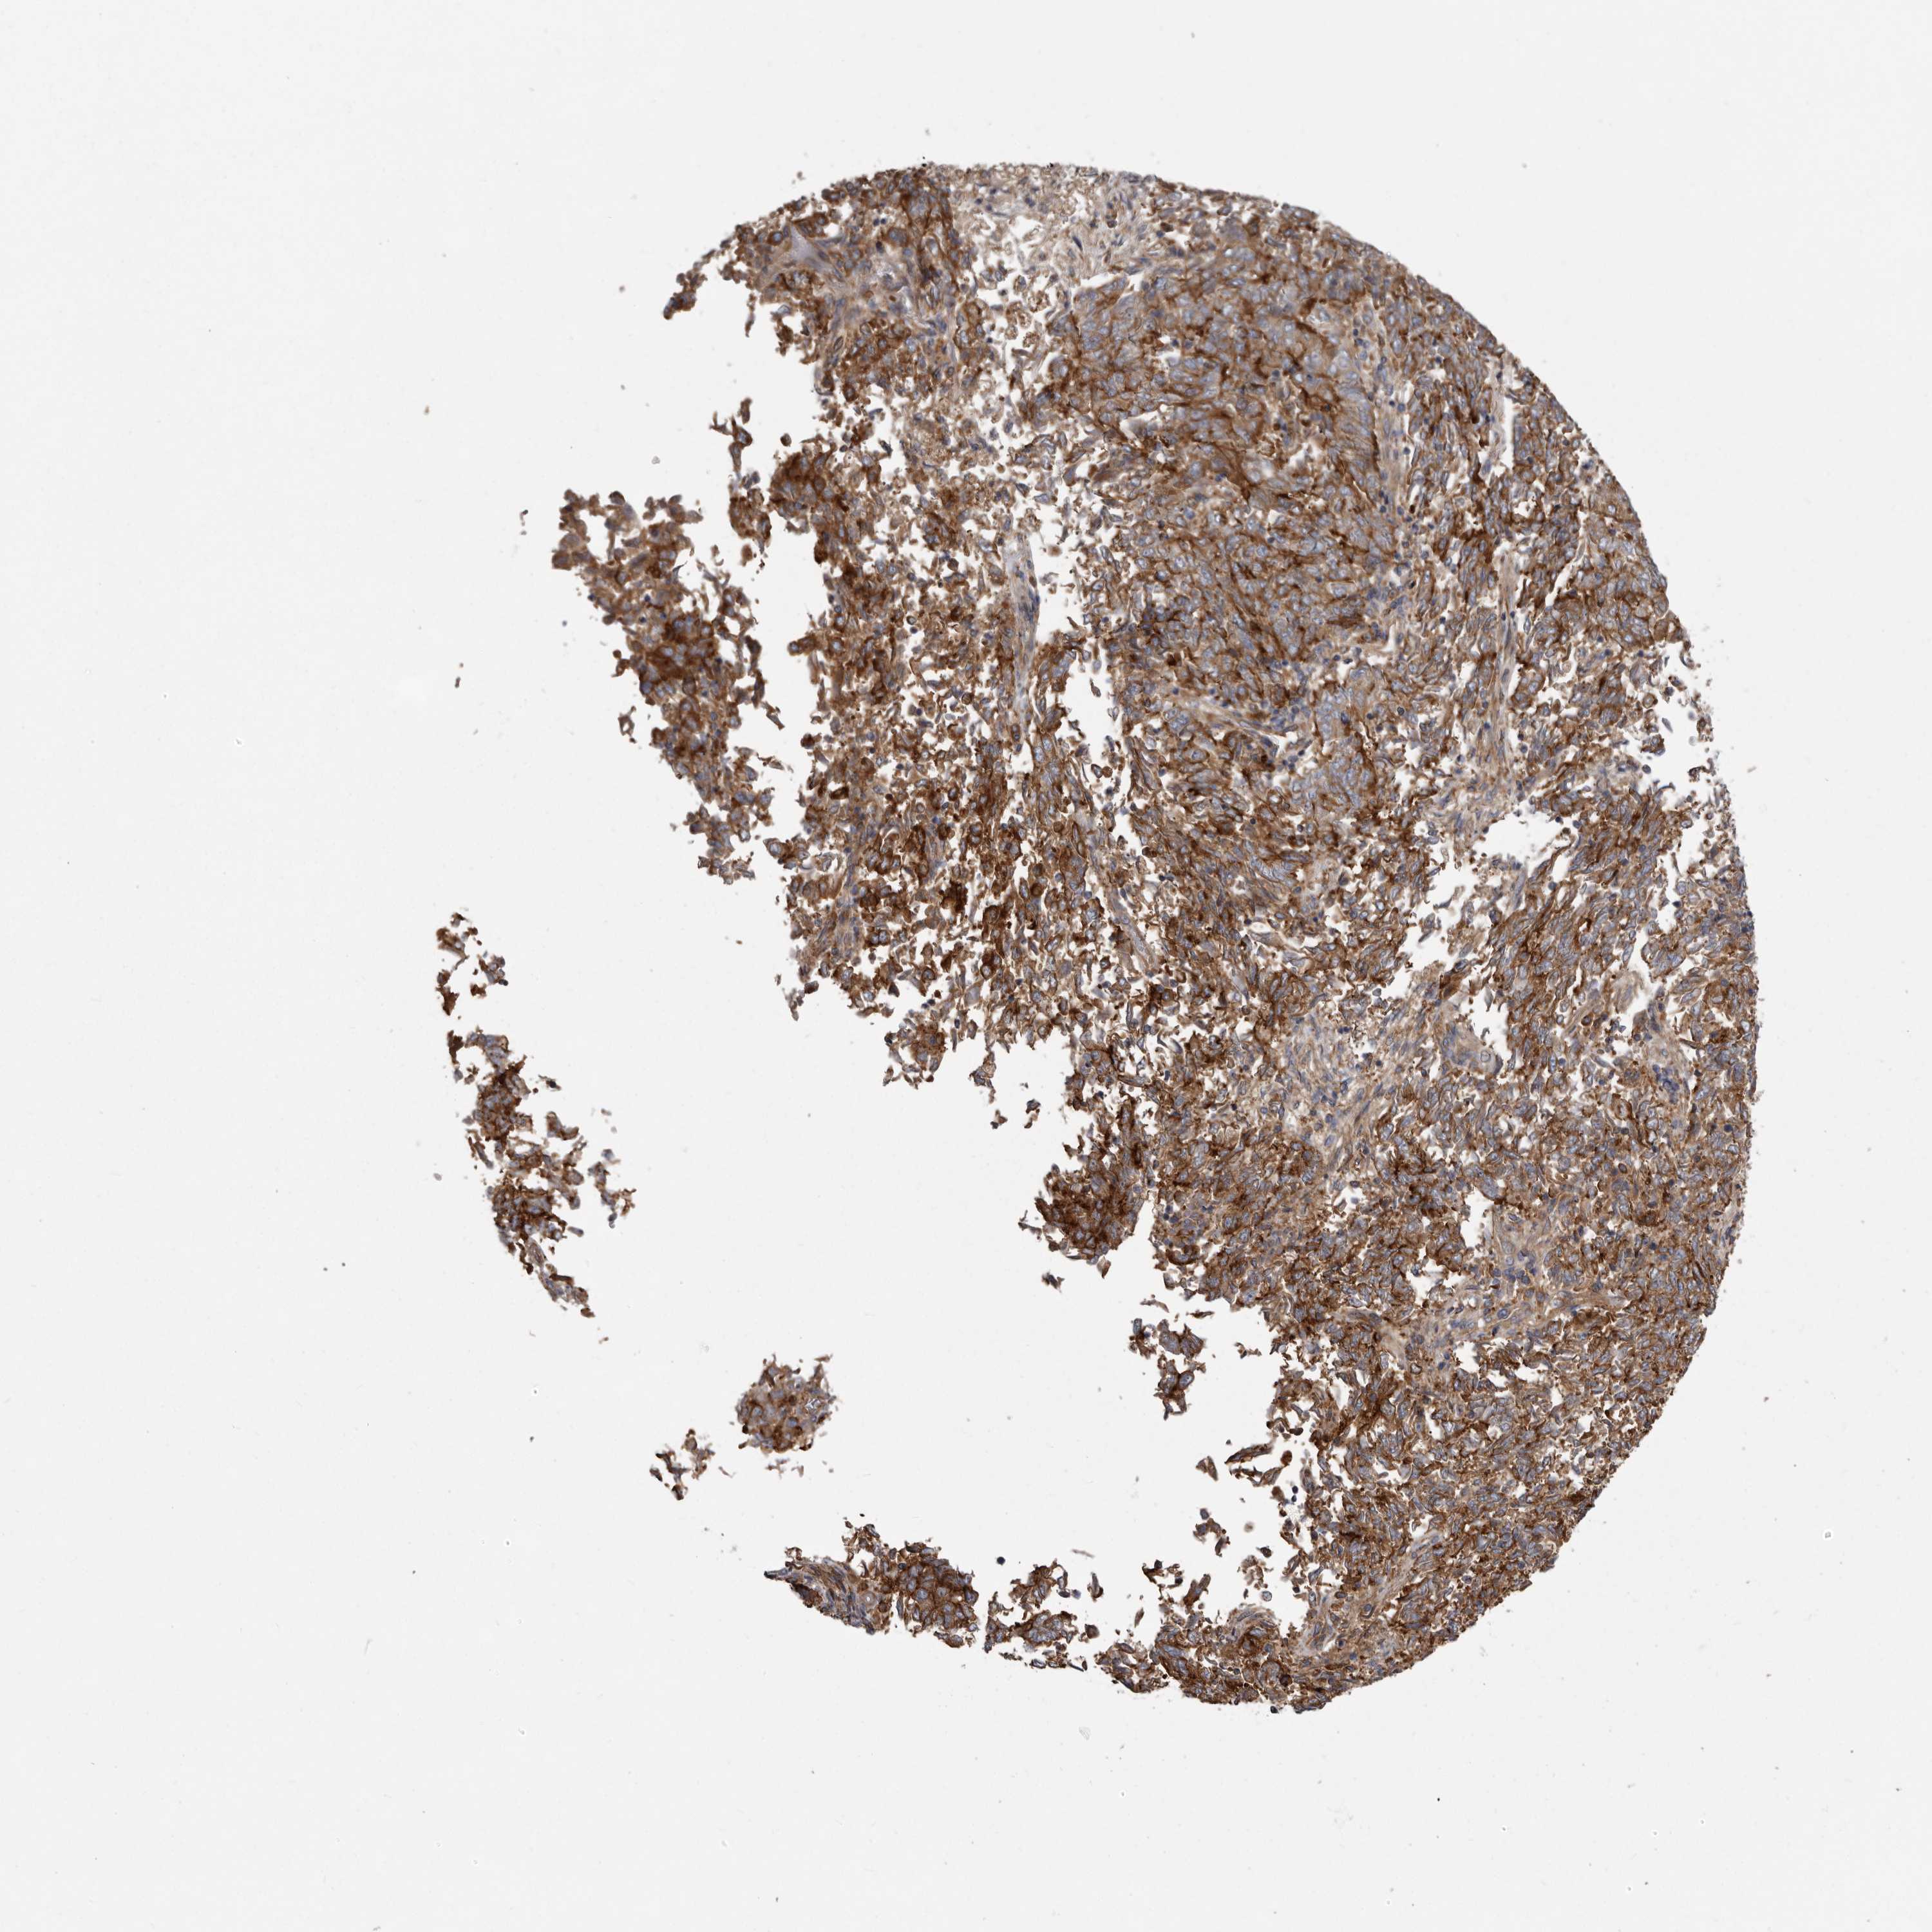

ENDOMETRIAL CANCER - Protein expressioni

A mouse-over function shows sample information and annotation data. Click on an image to view it in a full screen mode. Samples can be filtered based on level of antibody staining by selecting one or several of the following categories: high, medium, low and not detected. The assay and annotation is described here.

Note that samples used for immunohistochemistry by the Human Protein Atlas do not correspond to samples in the TCGA dataset.

Antibody stainingi

Antibody staining in the annotated cell types in the current human tissue is reported as not detected, low, medium, or high, based on conventional immunohistochemistry profiling in selected tissues. This score is based on the combination of the staining intensity and fraction of stained cells.

Each image is clickable and will lead to virtual microscopy that enables deeper exploration of all samples and also displays staining intensity scores, fraction scores and subcellular localization as well as patient and tissue information for each sample.

Antibody HPA028448

Antibody HPA028696

Staining

High

Medium

Low

Not detected

Intensity

Strong

Moderate

Weak

Negative

Quantity

>75%

75%-25%

<25%

None

Location

Nuclear

Cytoplasmic/membranous

Cytoplasmic/membranous,nuclear

Adenocarcinoma, NOS

Adenocarcinoma, metastatic, NOS